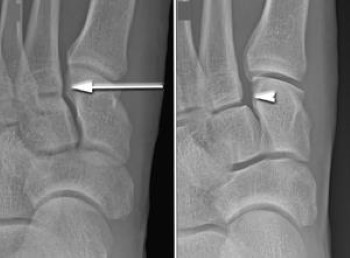

X-rays of Lisfranc injury

(Left) In this non-weightbearing X-ray, the Lisfranc injury does not show any abnormal widening (arrow). (Right) The tear of the Lisfranc ligament is more evident in this weightbearing stress X-ray, showing a widening of the joint.